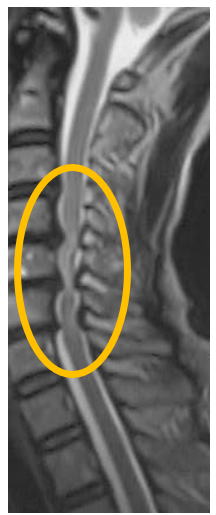

精緻な問診と、神経学的所見(腱反射検査、筋力テスト、知覚検査)で問題となる脊髄の障害部位を推察して、その領域に頸椎MRIで脊髄の圧迫所見が存在すれば診断確定となります。一般的に薬は効果が乏しく、脊髄の圧迫を緩める手術が必要になることが多いです。下記に頚椎症性脊髄症の頸椎MRIを示します。膨隆した椎間板や肥厚した靭帯が脊髄を圧迫していることが良く見えます。

脊髄症状に伴い、上図のごとくの脊髄圧迫がある時は、可及的早期に脊椎手術対応可能な病院へご紹介します。